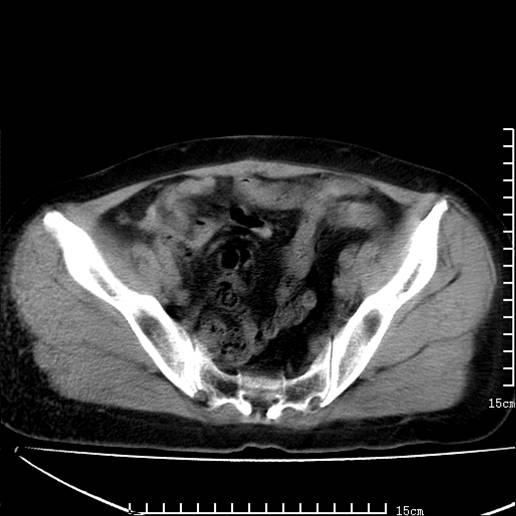

以下是引用pujunzhi在2008-5-30 15:31:00的发言:[br]异位肾—盆腔肾。当看到肾窝无肾脏时,要想到孤立肾和异位肾,异位肾最常见是盆腔肾,偶见胸腔,易误认为肺占位,只要想到就不会漏诊。建议增强扫描。